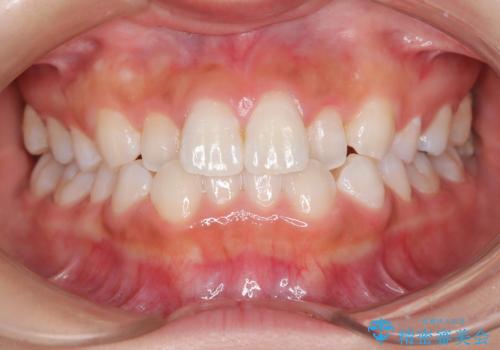

- 子供のころに矯正治療をされていたが、後戻りをしてしまったという20代女性の患者様です。上顎左右の2番が、咬合時に下顎の歯よりも内側に入っているクロスバイトという状態でした。奥歯の咬合関係は変えずに、マウスピース矯正にて前歯の並びを綺麗なアーチに仕上げました。再度後戻りしてしまうリスクを軽減させるために、リテーナー(保定装置)をお渡ししています。